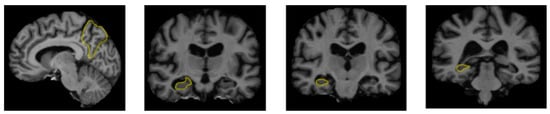

With advancements in medical technology, diagnostic techniques have also evolved. Brain scans, for instance, are utilized to detect Alzheimer’s by examining medical images for signs of brain atrophy or enlargement in certain areas. These scans, in particular, aim at brain regions including the hippocampus and the cerebral cortex since they are responsible for memory, speech, judgment and thinking activities, all of which are significantly altered by the advancement of AD [28].

A range of influences affect the onset of Alzheimer’s disease, among them lifestyle choices, cardiovascular health, head trauma, age, gender, genetic predispositions, infections, environmental influences, and pre-existing conditions like diabetes, as depicted in Figure 1. In individuals with Alzheimer’s, abnormal protein formations such as amyloid plaques and neurofibrillary tangles develop in and around neurons in specific areas of the brain [29]. These pathological changes lead to the deterioration and damage of brain tissues, as shown in Figure 2 [30].

Figure 2.

The regions of the brain affected by Alzheimer’s disease in MRI images [30].